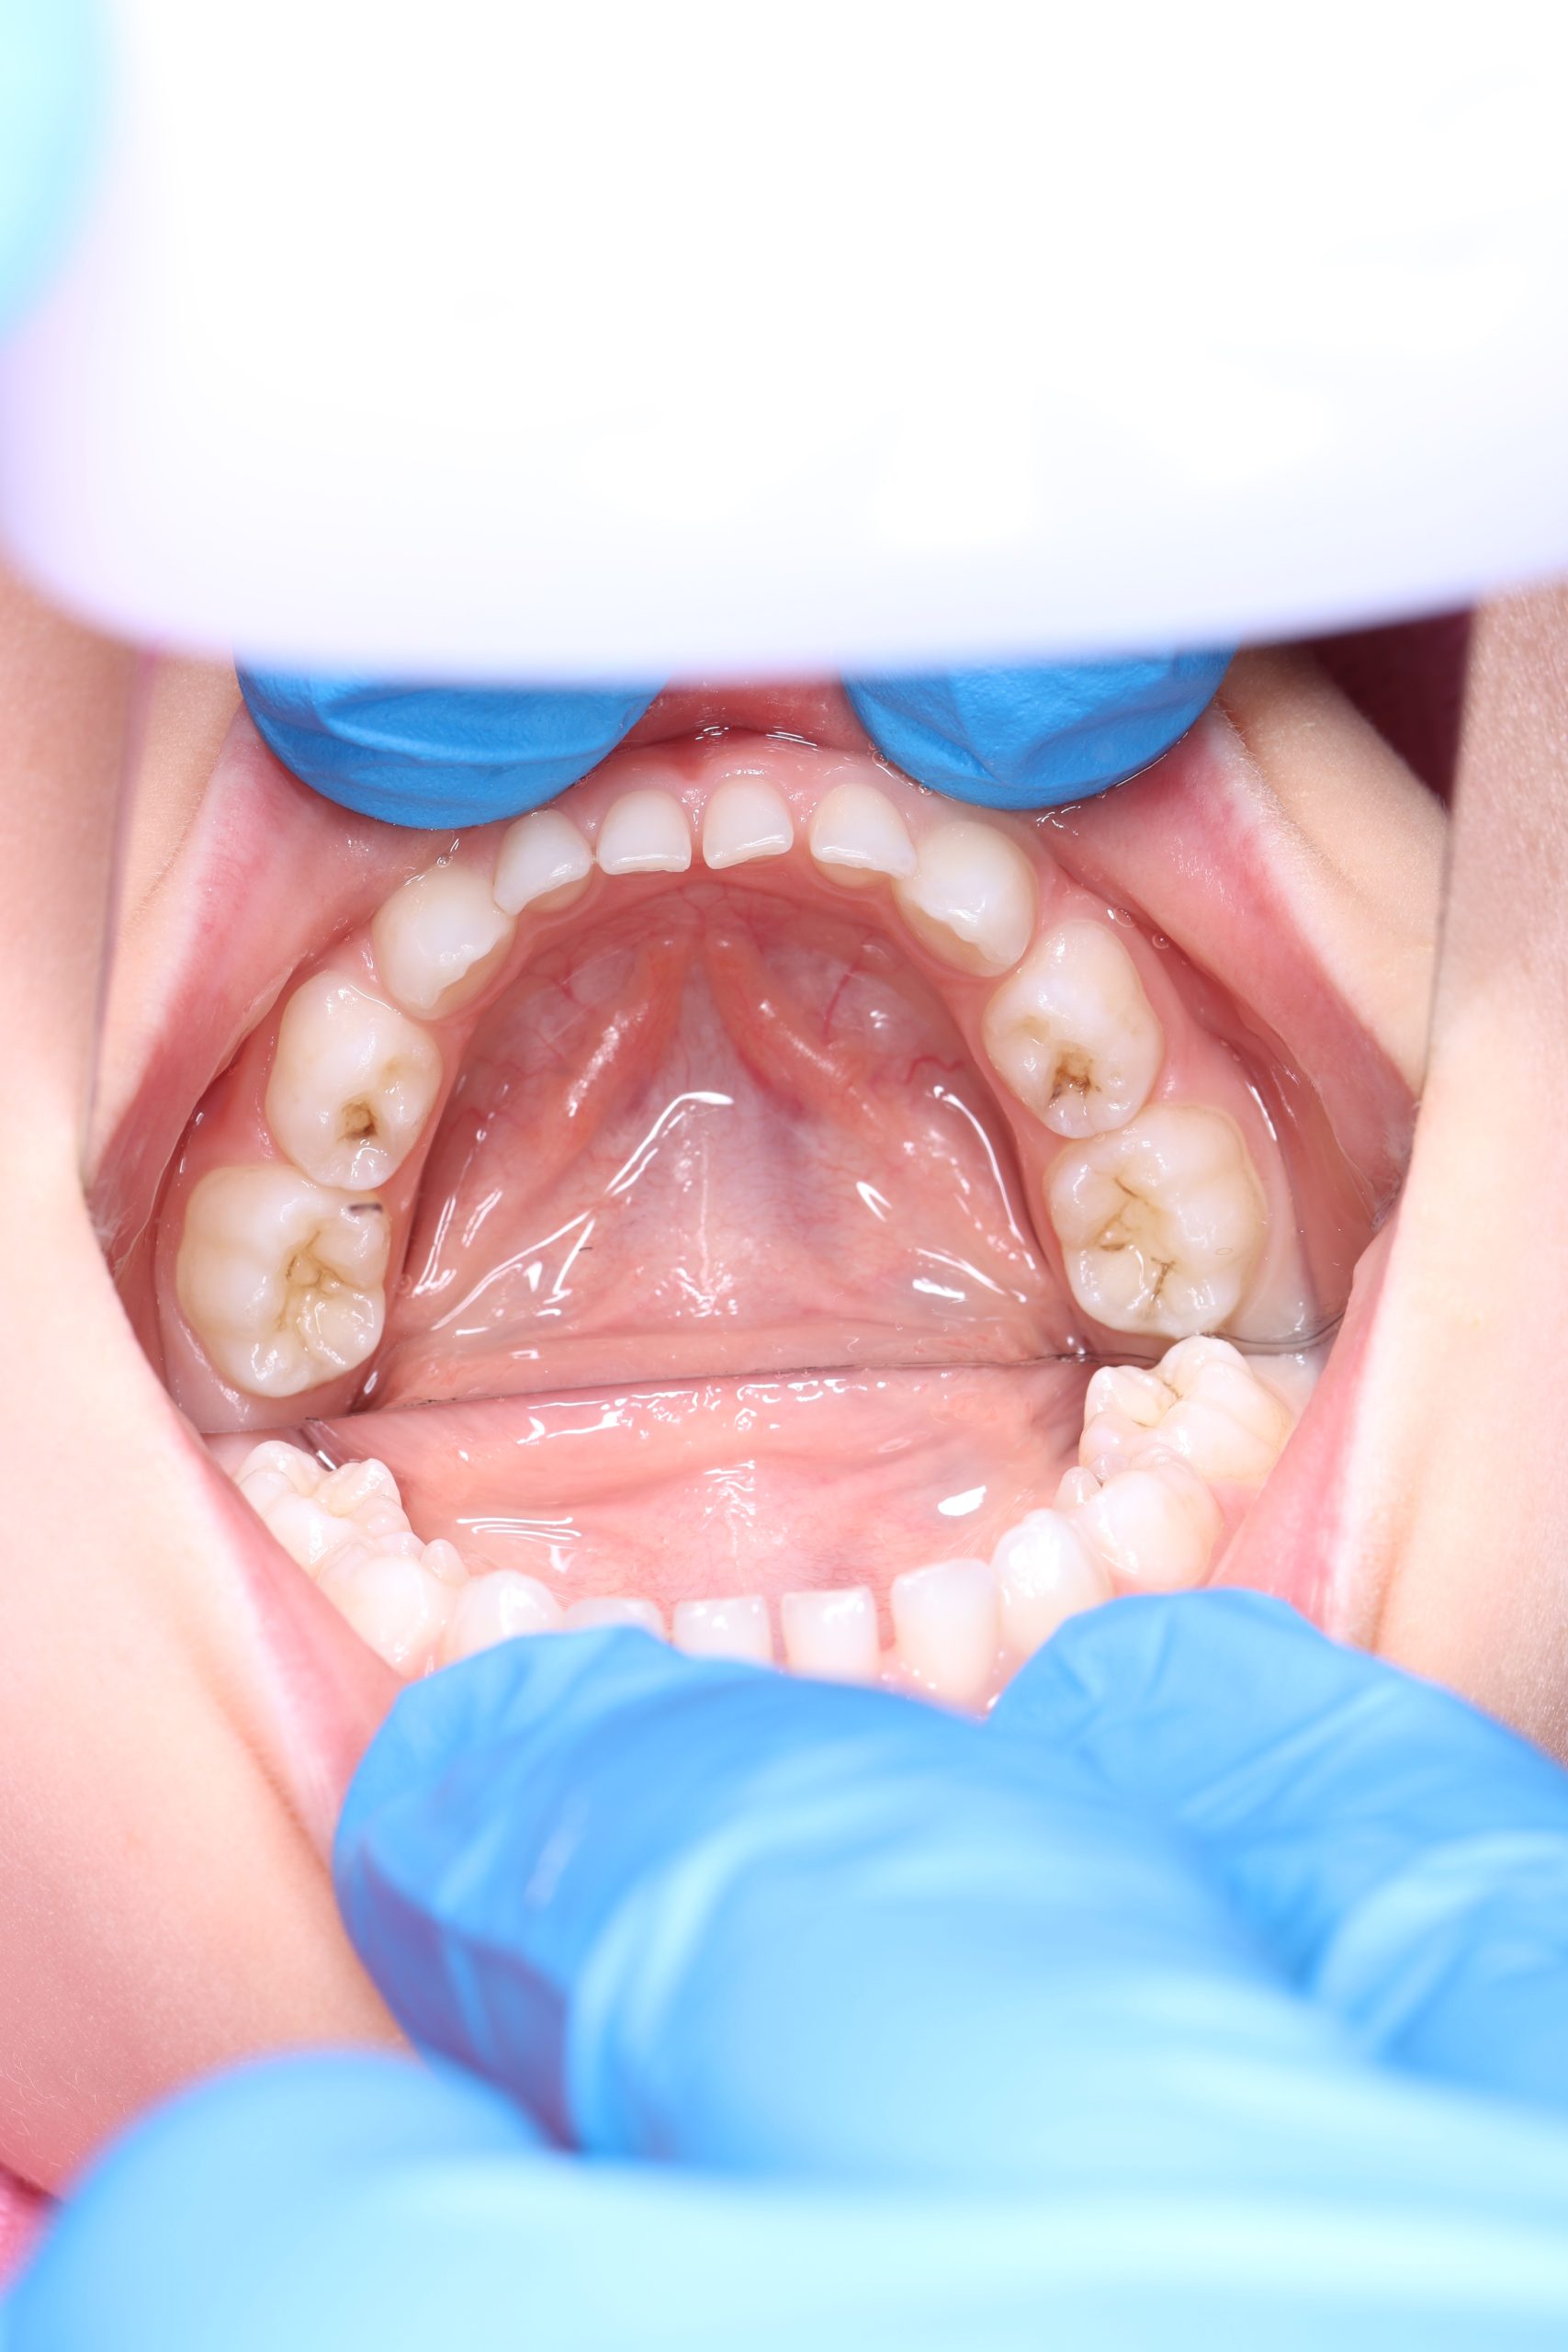

- Detailed Examination

We examine the condition of teeth, gums, and bite. - Plaque Disclosure with Special Indicators

Any tartar is removed gently and painlessly. - Final Check-Up + Fluoride Protection

We ensure the teeth are clean and free from early caries (even in the spot stage), then apply fluoride varnish to protect and strengthen enamel. - Personalized Recall Plan